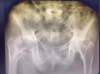

Masculino, 12 anos

Síndrome da sincondrose isquiopúbica assimétrica (Doença de Van Neck-Odelberg)

Variante da normalidade (em geral assintomático)

Crianças

Alargamento e radioluscência na sincondrose isquiopúbica, que simula neoplasias, infecção;